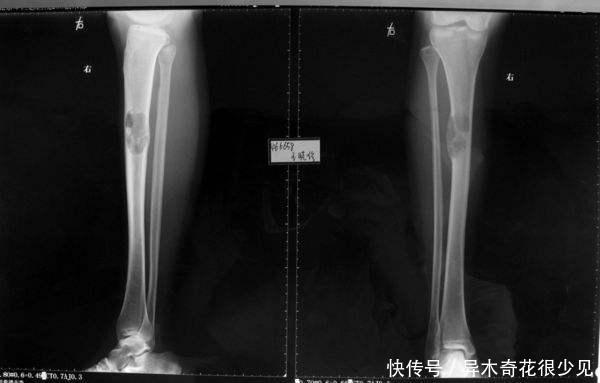

文章图片

骨肿瘤造成的病理性骨折

有的时候骨折就是肿瘤的一种首发症状。这种形式很特殊,正是因为骨骼被肿瘤所严重侵袭,骨骼原来能承受很强的压力,但是侵袭之后的骨骼不可以承受这些压力。

当一定的外力作用于受侵袭的骨骼时,就会出现骨折的症状,这种骨折称之为病理性骨折。临床上常常能见到轻微的外伤就可以引起这种病理性骨折。甚至可以看到有人拿起苍蝇拍打苍蝇,在这个过程中出现骨折的状况。这时候就要考虑病理性骨折的可能。